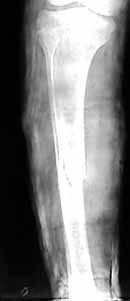

humerus

The patient came to me two days after injury. Her general condition was not good with Hb 6.7 gm%. After Blood transfusions in the first stage I did standard femoral Interlocking - 10mm nail with two proximal screws. 3 days later I did Tibial and Humeral Interlocking nailing - 8mm and 6mm nail respectively with proximal locking only.

On discharge 10 days later she wass walking independently with Zimmer frame with full knee hip and shoulder movements. Xrays are attached.